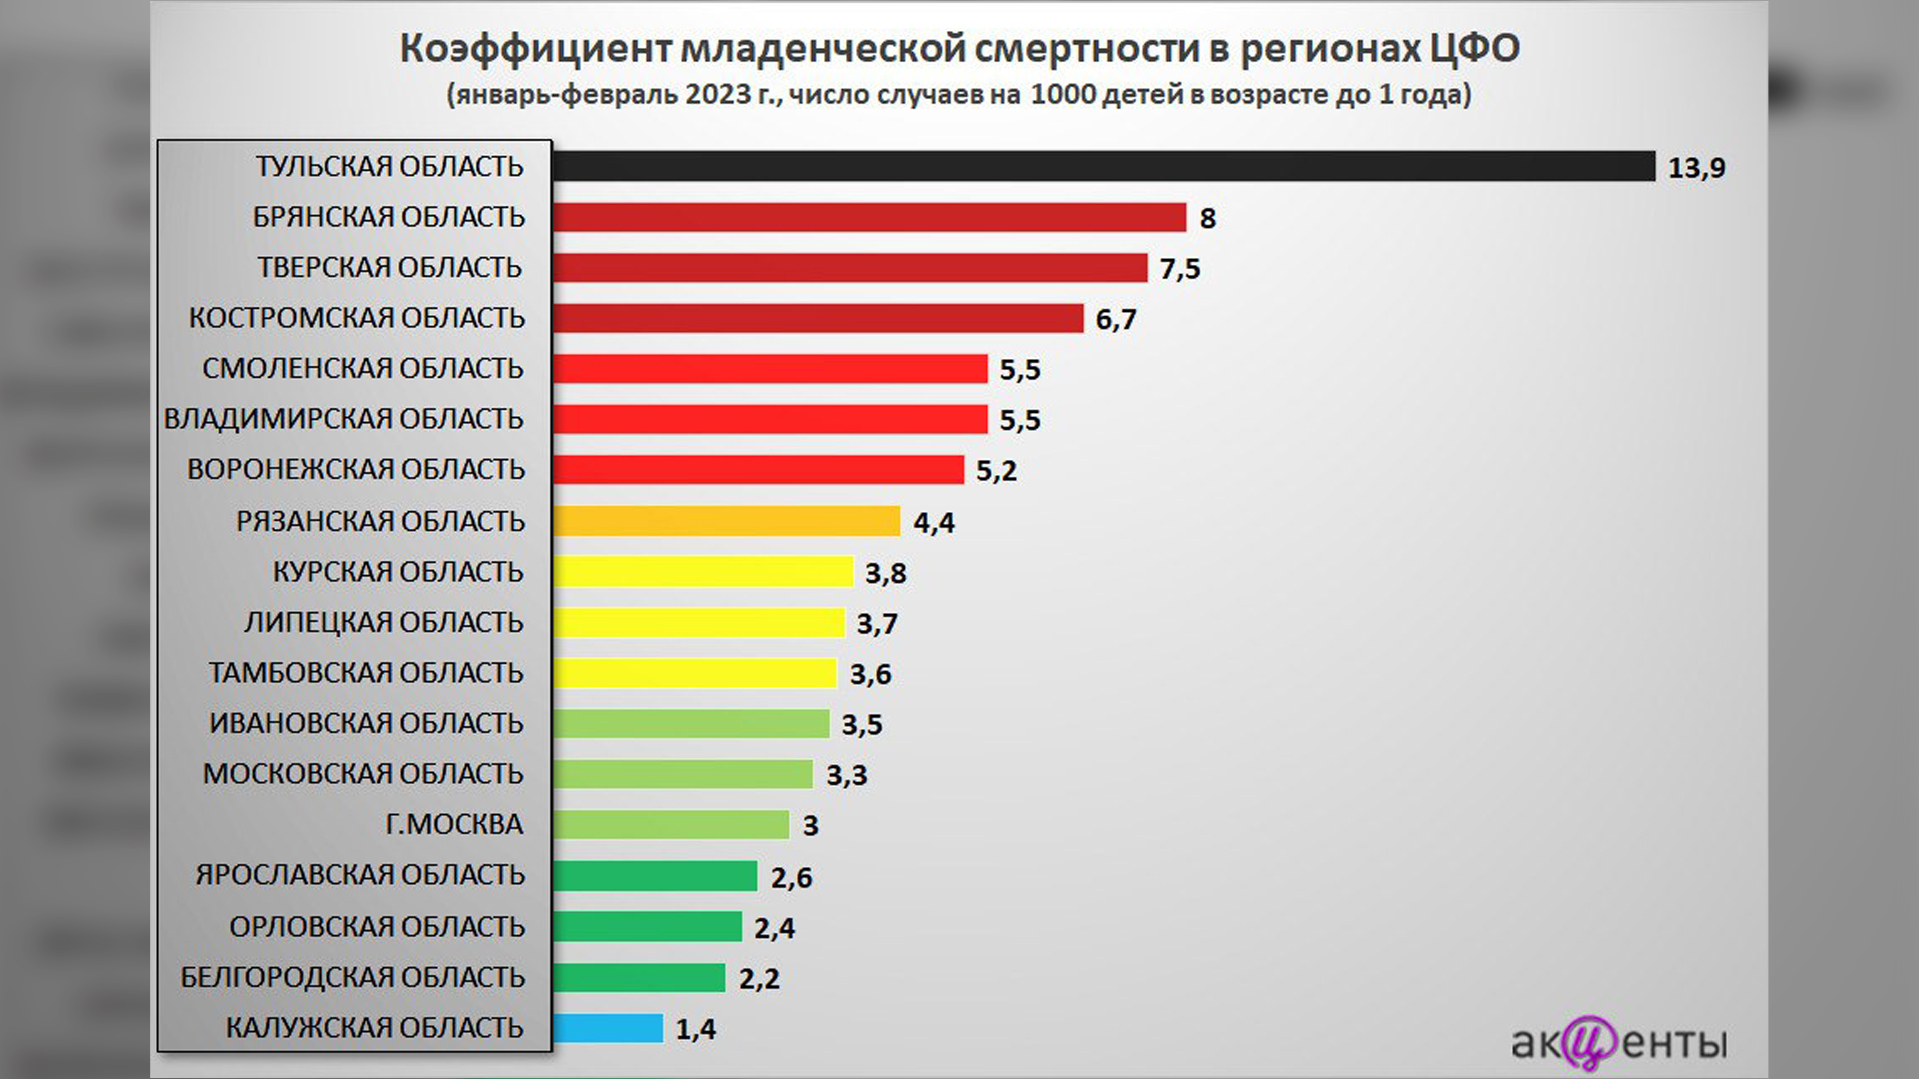

Владимирская область заняла шестое место в ЦФО по уровню младенческой смертности. Число случаев смерти детей в возрасте до года на 1000 малышей достигло 5,5, следует из антирейтинга telegram-канала «Акценты средней полосы», опубликованного в пятницу, 21 апреля.

Аналитики для исследования брали два первых месяца 2023 года. Владимирская область оказалась в красной зоне вместе со Смоленской и Воронежской областями.

Тульская область поставила всероссийский рекорд по младенческой смертности. Там число случаев смерти малышей на 1000 детей составил 13,9 за январь и февраль 2023 года. Следом в антирейтинге идет Брянская область – 8 случаев на 1000 малышей.